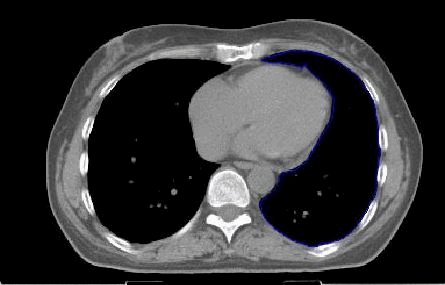

| Technik der perkutanen Bestrahlung |

Zielvolumen- Definition von Brust und Brustwand |

| Inspiration |

Die Bestrahlung in Inspiration kann Herz und Lunge besser schonen. |